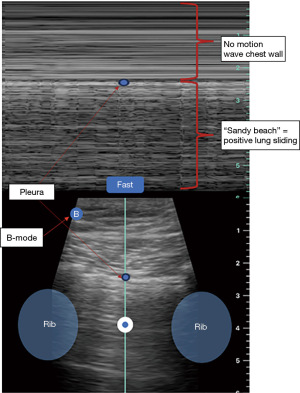

- Absence of lung sliding: normally, lung sliding is observed as a shimmering or gliding motion of the pleural line with respiration. This will be represented as a “sandy beach” appearance on M-mode (Figure 2) and will not be seen in patient with PNX.